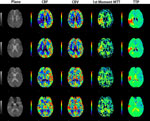

■ 脳血流解析

頭部領域においてダイナミックCTおよびMRのデータを画像処理し、脳の血流状態を定量的および視覚的に評価します。Deconvolutionを用いた脳血流量(CBF)/脳血液量(CBV)/平均通過時間(MTT)、TDCから算出した造影剤到達ピーク時(TTP)/平均通過時間(MTT)を計測してマッピングします。さらにMRでは1st

Moment法によるMTTの算出が可能です。 |